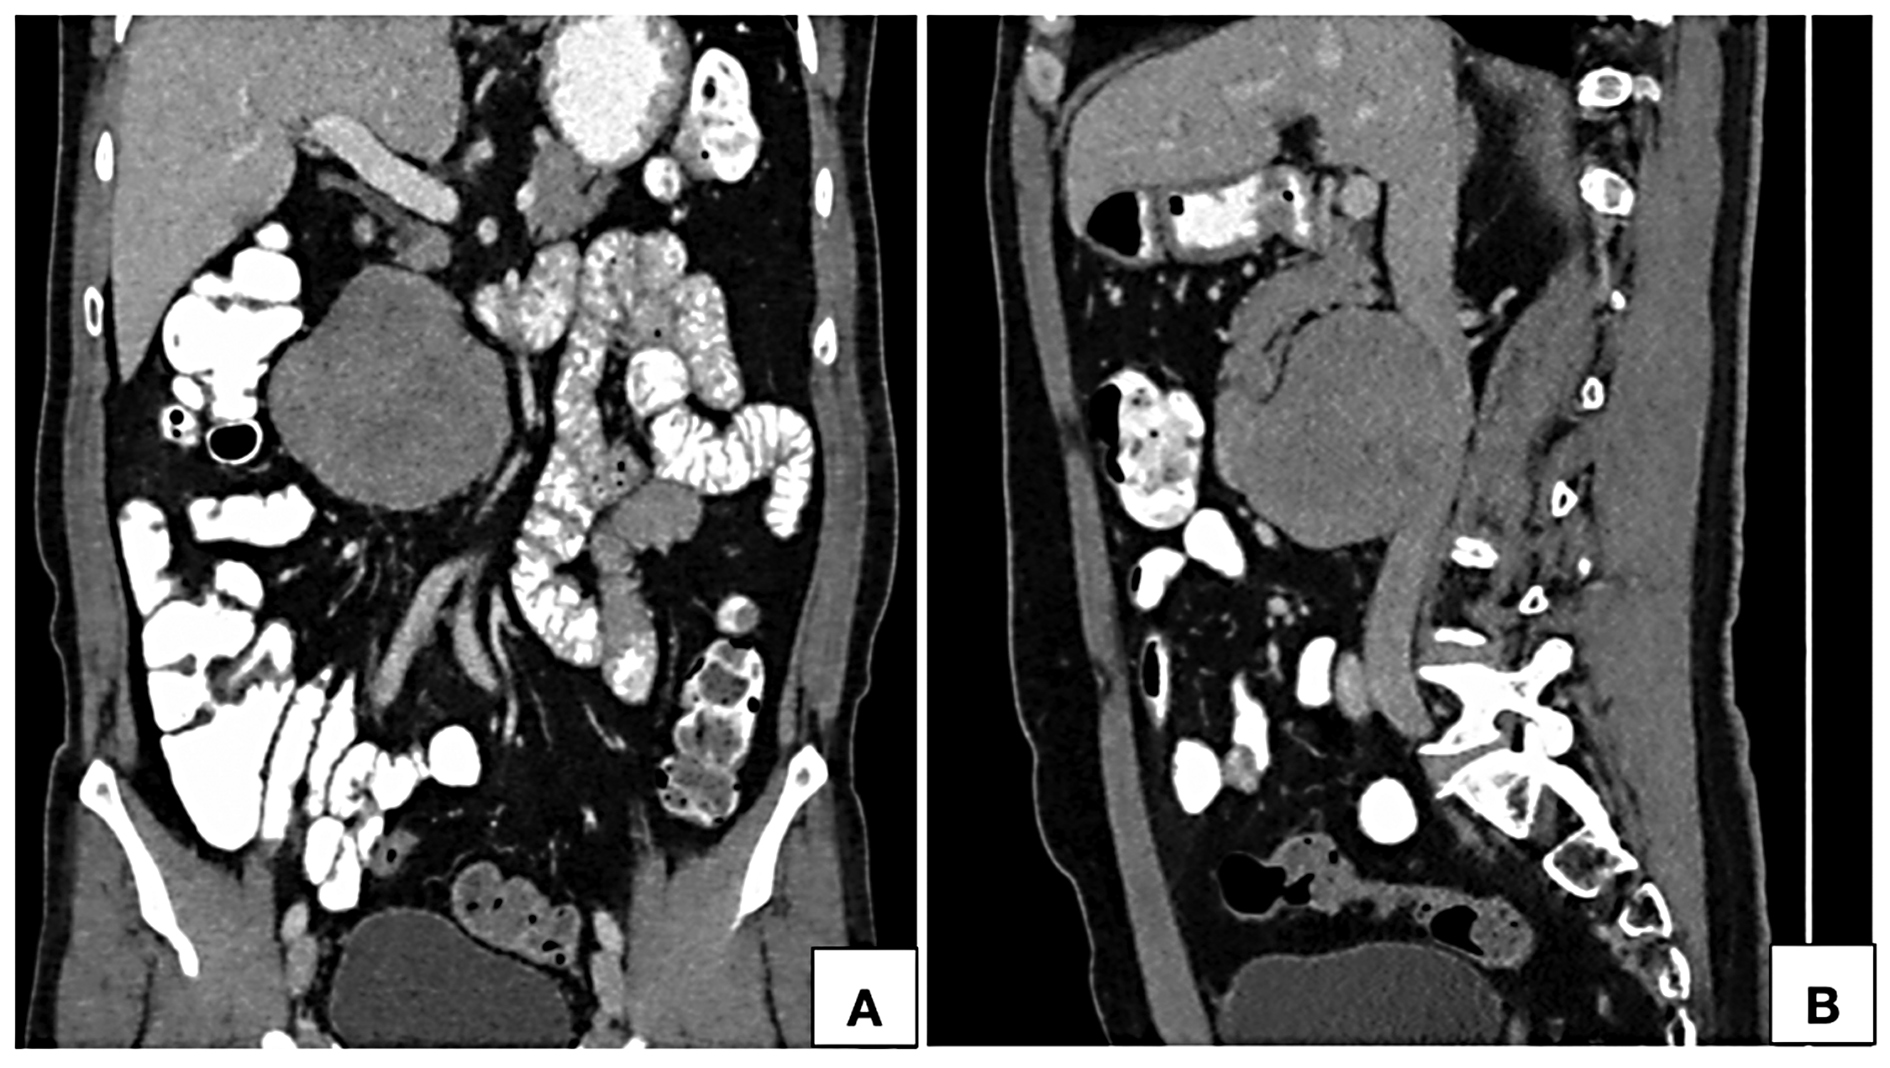

Routine ultrasonographic examination revealed a circumscribed hypoechoic lesion in the upper abdomen measuring 6.6 × 6.3 × 5.9 cm (CC × AP × Tr). For further evaluation, patient underwent computed tomography which revealed a circumscribed retroperitoneal soft tissue lesion in right side of midline, measuring 7.3 × 7.5 × 8.1cm (CC × AP × Tr). The lesion showed inhomogeneous contrast uptake on arterial phase and homogeneous enhancement on portal venous and delayed phases with few nonenhancing areas within. It was abutting the inferior vena cava posteriorly with imperceptible

lumen at the site of maximum contact. However, proximal and distal segments of the inferior vena cava showed normal contrast opacification. Medially, the lesion was in relation to the abdominal aorta. Second and third part of duodenum and head of pancreas were displaced anterosuperiorly. Magnetic resonance imaging (MRI) showed a homogeneously enhancing circumscribed lesion in the retroperitoneum on right side of midline appearing isointense on T1W, hyperintense on T2W showing restricted diffusion. Few cystic areas were seen within the lesion. On prone imaging, the lumen of inferior vena cava was still imperceptible at the site of maximum contact. No obvious intraluminal extension was seen. Whole body positron emission tomography CT revealed mild FDG uptake with a maximum standard uptake value (SUVmax) of 4.1. No distant metastases were found.

One of the important imaging feature for characterization of retroperitoneal tumors is the relationship with IVC. Webb Em et al [27] undertook a retrospective analysis of 13 cases of retroperitoneal tumors to study the performance of four different radiological signs in differentiating LMS of IVC from other primary retroperitoneal tumors. Radiological signs that were studied are positive embedded sign, negative embedded sign, imperceptible IVC sign and tumor in lumen. They observed that imperceptible IVC lumen at the site of maximum contact is highly predictive of a IVC origin. Case described in this manuscript had the imaging feature. Prone imaging can be of diagnostic utility in demonstrating primary origin from IVC in patients with predominantly extraluminal lesion. On prone imaging, these tumors show persistent contact with the wall of IVC or persistent nonvisualization of the lumen of IVC. Tumors with predominant extraluminal component commonly occur in anterior relation to the IVC and towards the right side of midline [9-11, 17, 19]. However, tumors originating posteriorly from the IVC have also been reported [5, 14].

These tumors commonly show heterogeneous enhancement with areas of necrosis within [9, 14, 15]. Sessa B et al [10] reported inhomogeneous early enhancement followed by homogenous filling in portal venous phase. We observed inhomogeneous contrast uptake in arterial phase followed by near homogeneous enhancement in portal venous and delayed phases with nonenhancing areas within. Few authors have also reported presence of calcification [16, 25] and hemorrhage [26] within the lesion.